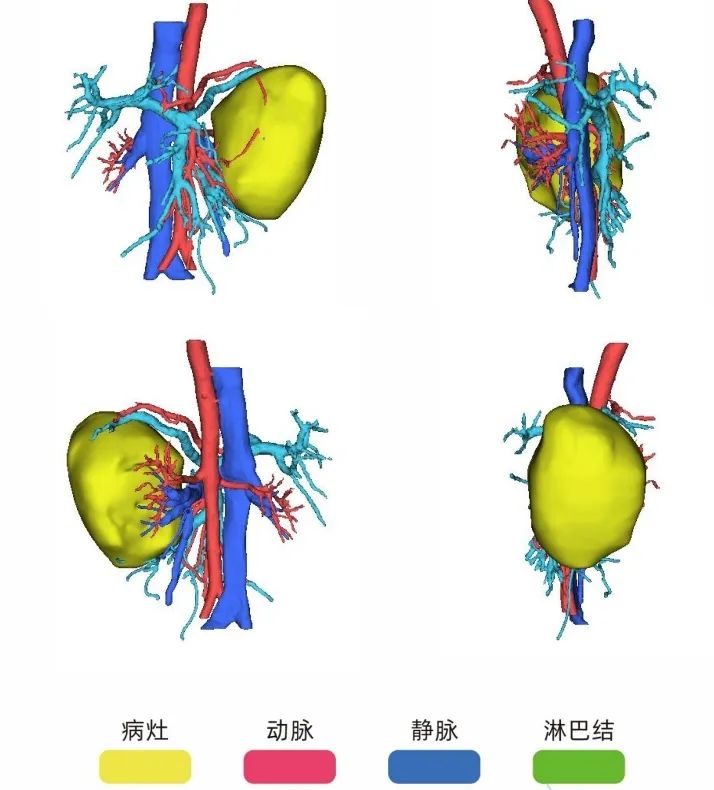

相较于传统的二维图像,三维可视化模型具备更直观、更精确的特点。模型可以实现全方位旋转、任意缩放和组合显示,能够清晰展示肿瘤的大小、形态,血管的走向和形态,更深入地揭示肿瘤与周围器官及血管的解剖关系和侵犯情况,减少了医生在解读原始CT图像时可能出现的主观失误,使术前评估更加真实可靠。

三维重建可辅助手术规划设计,通过三维重建,可以提供更多关于肿瘤的信息,包括肿瘤边界整体形态、血液供应情况以及与肾血管的关系。

三维重建技术可以精确观察肾血管的起始位置及走形、数量和间距,从而选择合适的阻断血管及阻断位置,减少因阻断不全而引起的出血。

三维重建技术展现出其独特的优势,能够更为直观、准确地展示肿瘤位置以及与周围血管之间的关系,为手术决策提供有力的支持。

三维重建技术可以提供肾脏肿瘤的地形图和肾内解剖的多平面视图,从而有助于精确规划肾脏肿瘤的手术。该技术在重建肿瘤周围的解剖结构、微小血管和组织方面具有高度准确性,能够为患者创建个性化的3D模型,有助于外科医生更直观、更深人地了解病情。

对于复杂肾肿瘤的保留肾单位手术以及普通影像预估血管解剖关系复杂的肾肿瘤,建议术前三维重建评估。对于行高选择性阻断及免阻断保留肾单位手术,建议术前行三维重建评估肿瘤血供。以便辅助手术决策,做好充分的术前规划。